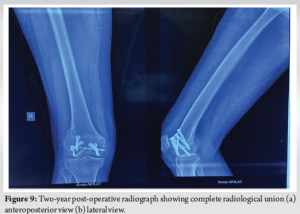

The patient was followed up in the outpatient department at 2 weeks, 6 weeks, 3 months, 6 months, 1 year, and 2 years. Toe touching weight-bearing was started at 2 weeks and gradually progressive knee ROM was allowed through the hinged knee brace. At 6 weeks, the patient had regained a ROM of 5–90° and weight-bearing to tolerance was encouraged on the affected limb alongside regular physiotherapy sessions. At 3 months, the patient had achieved a ROM of 5–100°, which further improved to 0–120° at 6 months. At 1 year, the ROM was 0–140° with full weight-bearing on the affected limb. At 2 years post-operatively, the X-ray showed complete radiological union and the patient had achieved full ROM, with no extensor lag and was able to bear full weight on the affected limb with little to no pain in the affected limb (Fig. 7 and 8).

The mechanism involved in a double Hoffa fracture typically involves an axial load on a flexed knee, resulting in shear forces sufficient to split both femoral condyles in the coronal plane. The exact mechanism causing a simultaneous fracture in both the femoral condyles is largely unknown. The most probable mechanism can be assumed to be a posterior and upward-directed force without any varus or valgus component, in a flexed knee [4]. CT imaging is essential for accurate classification and planning, as conventional radiographs may not reveal the exact fracture pattern, especially if the fracture is undisplaced. Given the unique fracture morphology in our patient – a true double Hoffa fracture without metaphyseal comminution or intercondylar extension – an individualized approach was necessary. Ul Haq et al., described the management of a similar case of a conjoint bicondylar Hoffa fracture, where both the femoral condyles were joined by a bridge of intact bone, fixed with cancellous screws, leading to a favorable outcome [4]. Zeebregts et al. and Papadopoulos et al., also described similar cases treated through separate medial and lateral approaches, fixed with 6.5 mm cannulated screws [5,6]. In contrast, our approach through a single medial parapatellar exposure facilitated adequate visualization of both fractured condyles and reduced soft tissue damage. Furthermore, a direct midline approach allowed us to put screws perpendicular to the fracture line, in accordance with principles of fracture fixation. Agarwal et al., managed such bicondylar coronal fractures with cortical lag screws and plating [7]. However, given the absence of metaphyseal comminution in our case, plating was not deemed necessary. Dua and Shamshery also reported a similar bicondylar Hoffa fracture managed successfully using a Swashbuckler approach, and five 6.5 mm cannulated screws for fixation of the Hoffa fragments, augmented with a condylar buttress plate on the lateral aspect [8]. Similarly, Giotikas et al., used a dual plating technique in the presence of metaphyseal comminution – a feature not seen in our patient [9]. Our decision to use multiple screws on both sides was guided by the presence of subtle comminution and the need for rigid fixation to allow early mobilization. The functional outcome in our patient was remarkably favorable, emphasizing the importance of anatomical reduction, rigid fixation, and early rehabilitation [10]. The ability to regain full ROM without extensor lag by 6 months reflects both the stability of fixation and the biological healing potential in young adults. (Fig. 9).